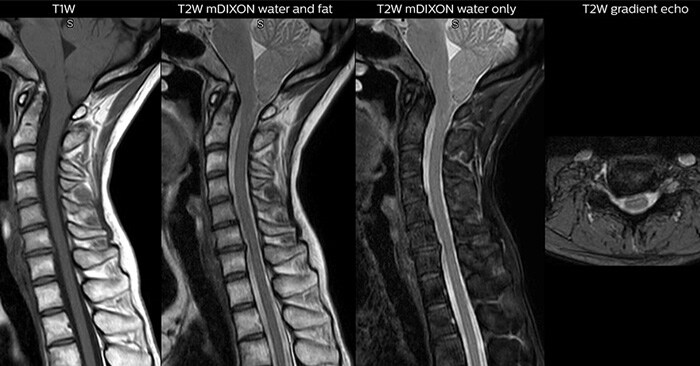

Through Philips mDIXON XD fat suppression application, we can help radiology teams achieve robust capturing of fat-free MRI images in a hectic ED environment. This technology brings a new dimension to fat-free imaging suppression by providing uniform, complete and consistent fat-free images as well as images with both water and fat at the same time, especially useful when time is of the essence Robust with regard to susceptibility-type problems that come up with traditional spectral fat-free images, mDIXON XD can bring speed and clarity to MRI imaging.

High lipid concentration of adipose tissues can make it difficult to interpret MRI exams. Information can be missed when the right acquisitions, such as with as well as without fat suppression, are not included. While this can be solved by adding sequences, this adds to the duration of the exam and increases the likelihood for patient motion – a source of image degradation.

Utilizing MR in the emergency department means a prioritizing speed to enable a quick diagnosis. However, accelerating scans can compromise imaging quality and can result in blurry images. Through Compressed SENSE, an application that enhances productivity in imaging by increasing the data that is able to be pulled quickly from scans, including both 2D and 3D scans, all anatomical contrasts and all anatomies.